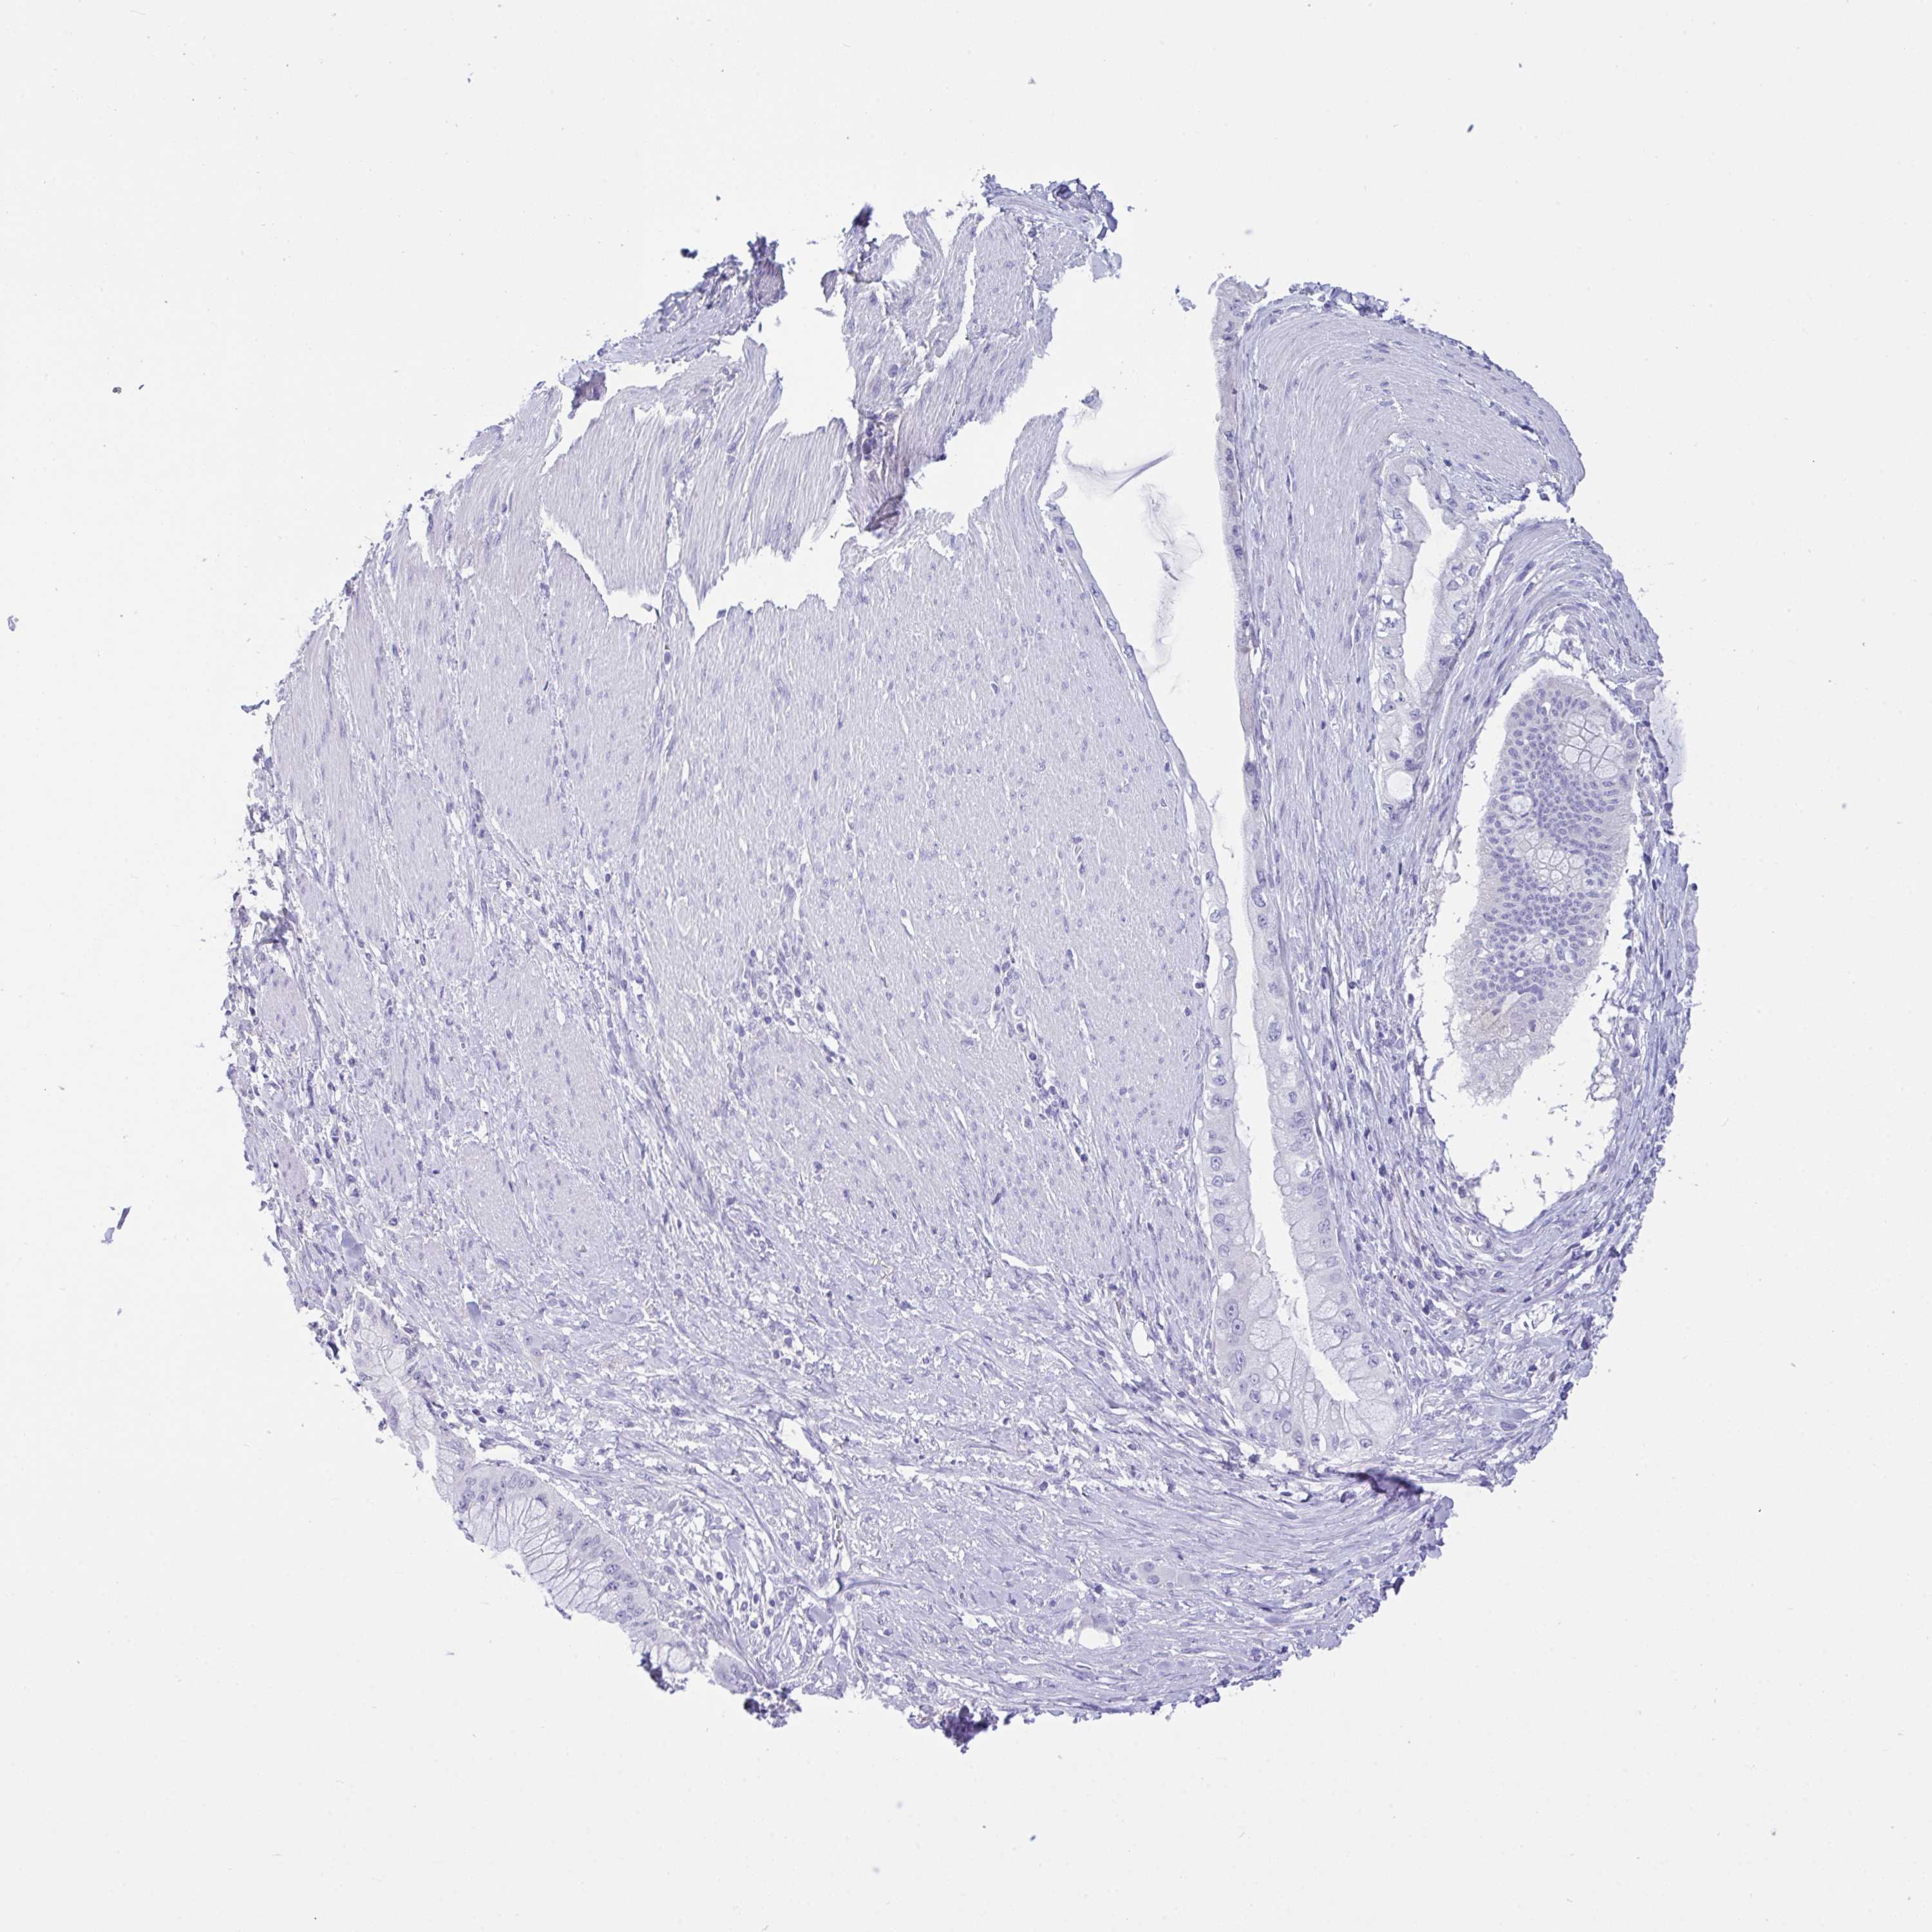

PANCREATIC CANCER - Protein expressioni

A mouse-over function shows sample information and annotation data. Click on an image to view it in a full screen mode. Samples can be filtered based on level of antibody staining by selecting one or several of the following categories: high, medium, low and not detected. The assay and annotation is described here.

Note that samples used for immunohistochemistry by the Human Protein Atlas do not correspond to samples in the TCGA dataset.

Antibody stainingi

Antibody staining in the annotated cell types in the current human tissue is reported as not detected, low, medium, or high, based on conventional immunohistochemistry profiling in selected tissues. This score is based on the combination of the staining intensity and fraction of stained cells.

Each image is clickable and will lead to virtual microscopy that enables deeper exploration of all samples and also displays staining intensity scores, fraction scores and subcellular localization as well as patient and tissue information for each sample.

Antibody HPA054825

Staining

High

Medium

Low

Not detected

Intensity

Strong

Moderate

Weak

Negative

Quantity

>75%

75%-25%

<25%

None

Location

Nuclear

Cytoplasmic/membranous

Cytoplasmic/membranous,nuclear

Adenocarcinoma, NOS